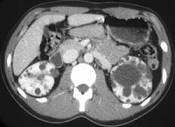

问题 男性,40岁,因腰痛血尿就诊,B超检查发现肾脏增大,CT表现如图所示,追问病史发现家族中有类似疾病,最可能考虑为 ( )

选项 A.多囊肾 B.肾积水 C.多发性肾囊肿 D.肾肿瘤 E.肾结核

答案 A